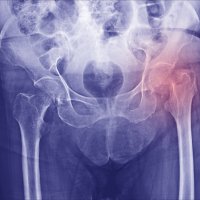

Skandinavia har den høyeste hyppigheten av hoftebrudd i verden, og hoftebrudd er et alvorlig folkehelseproblem (1–2).

Rundt 9800 pasienter rammes årlig i Norge (3), og ved Akershus universitetssykehus opereres om lag 600 av disse pasientene. Pasientgruppen består hovedsakelig av eldre som har falt fra egen høyde og kommer inn som øyeblikkelig hjelp. De har ofte redusert allmenntilstand, flere diagnoser og sammensatte fysiske, psykiske og sosiale problemstillinger (2–6).